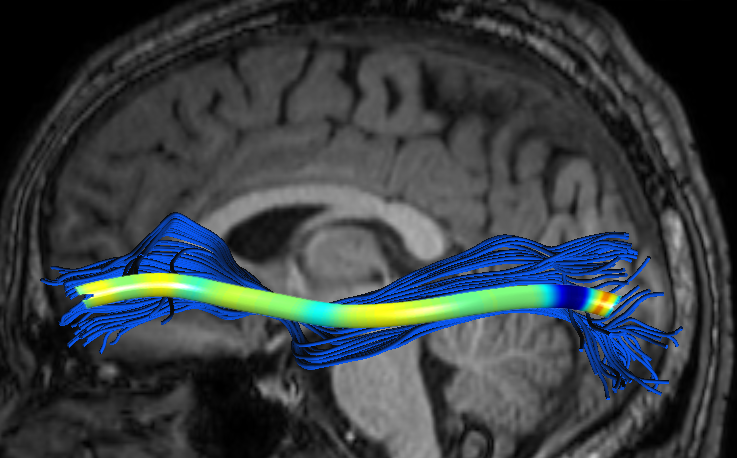

We performed pairwise comparison between two scans of a 32-year-old basketball player, diagnosed with mild occipital traumatic brain injury and frontal hemorrhage due to contrecoup impact, acquired one week and 6 months post-injury. The hemorrhagic lesion at the frontal right hemisphere of the player is no longer visible in the FLAIR image acquired 6 months after injury (Fig. 2a). Local differences between corresponding, longitudinal FA- and MD-FFDD profiles of the FMT (chosen due to its proximity to the lesion area) are shown in Fig. 2d. Figs. 2b-c present color-coded FMT to visually demonstrate these differences. Results show significant longitudinal variability at the right hemisphere part of the tract, corresponding to the lesion area, and relatively minor differences along the rest of the tract. These results should be considered as a proof of concept, validating the FFDD analysis results for the detection and localization of mTBI-related variabilities between fiber bundles.

| ONE WEEK | ![]() |

![]() |

FA-FFDD |

| 6 MONTHS | ![]() |

MD-FFDD |

| (a) FLAIR | (b) FA-FFDD | (c) MD-FFDD | (d) Local Differences |